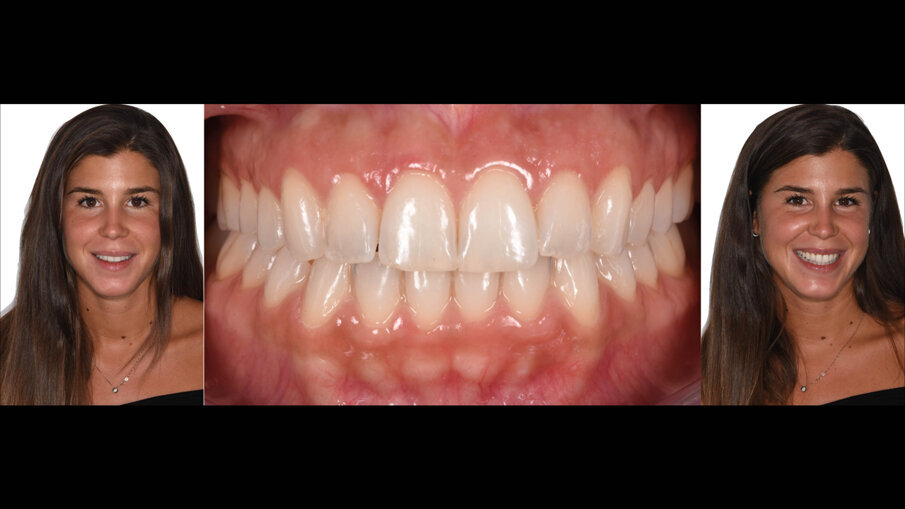

La suture, in questo caso 5.0 riassorbibili (Flysorb mono, Butterfly, Cavenago Brianza, MI) hanno il solo scopo di mantenere i tessuti molli nella posizione corretta per agevolarne il riattacco e la guarigione, i nodi quando possibili vengono applicati sul versante palatale (Fig. 15). A novanta giorni dalla chirurgia si può apprezzare l’ottima guarigione e maturazione dei tessuti e come l’interfaccia dente gengiva sia migliorata sia all’esame intra che extra-orale (Fig. 16). Le foto intra ed extra-orali fatte a 24 mesi dall’intervento testimoniano l’ottimo risultato ottenuto e la sua stabilità (Fig. 17).

Fig. 17_Followup a 24 mesi.